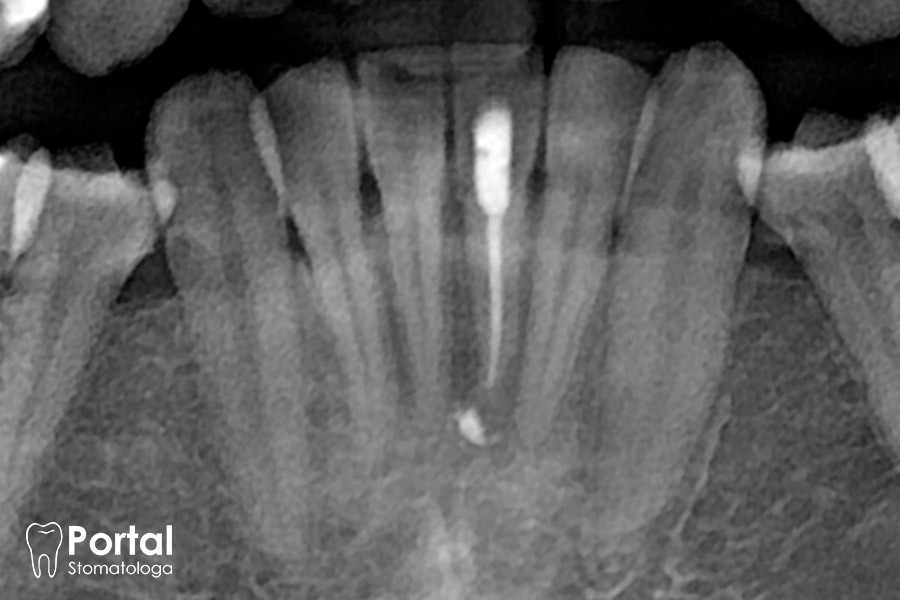

RVG zęba

RVG zęba to innowacyjna radiowizjografia (zdjęcie rentgenowskie) polegająca na uzyskaniu cyfrowego obrazu pojedynczego zęba lub jego niewielkiego fragmentu. Dzięki nowoczesnemu cyfrowemu sprzętowi RTG obraz pojawia